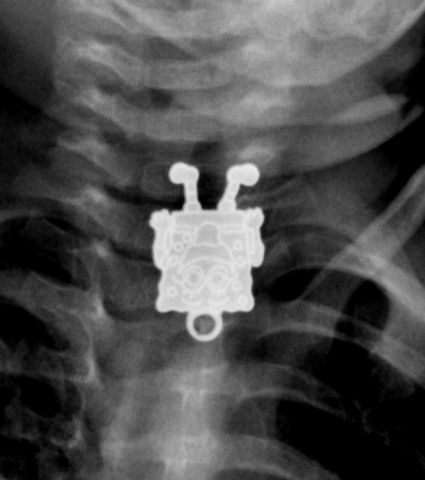

Ο κόσμος είναι ένα ενδιαφέρον μέρος, και τα νήπια (και τα μικρά παιδιά) τον ανακαλύπτουν εξερευνόντας τον, με όλες τους τις αισθήσεις ακόμα και την γεύση και την αφή. Είναι λοιπόν αναπόφευκτο να προσπαθήσουν να “δοκιμάσουν” οτιδήποτε βρίσκεται στο άμεσο οπτικό τους πεδίο. Για αυτόν τον λόγο, η πλειονότητα περιστατικών κατάποσης ξένου σώματος, αφορά ηλικίες 6μηνών – 6ετών και το 98% και περιλαμβάνει γνώριμα αντικείμενα όπως κέρματα, παιχνίδια, κοσμήματα, μπαταρίες και μαγνήτες

Σε πιο σοβαρές περιπτώσεις μπορεί να εμφανιστούν συμπτώματα όπως αίσθημα πνιγμονής, σιελόρροια, έμετος, δυσφαγία / άρνηση λήψης τροφής, συριγμός ή αναπνευστική δυσχέρεια. Για την εκτίμηση αυτών των περιστατικών, λαμβάνεται το κλινικό ιστορικό, καταγράφεται η ώρα κατάποσης, το είδος και μέγεθος του αντικειμένου ενώ ακολουθεί κλινική εξέταση και ανάλογα με το περιστατικό, ακτινολογικός έλεγχος (α/α θώρακος – κοιλιάς) για την εντόπισή του (αεροφόροι οδοί – οισοφάγος - στόμαχος)

Αν και ~65% των υλικών είναι ακτινοσκιερά, υπάρχουν αρκετά (π.χ. γυαλί – πλαστικό – ξύλο) τα οποία δεν “φαίνονται” στην ακτινογραφία , οπότε σε ισχυρή υποψία ή επί κλινικών συμπτωμάτων, είναι αναγκαία η περεταίρω εξέταση από ΩΡΛ ή η διενέργεια ενδοσκόπησης, και σπανιότερα άλλης απεικονιστικής εξέτασης

Όσο αφορά το υλικό των ξένων σωμάτων δίδεται ειδική προσοχή Στις παρακάτω κατηγορίες:

-Οι μικροί μαγνήτες είναι ακόμα ένα επικίνδυνο υλικό. Εάν το παιδί καταπιεί δύο ή περισσότερους ή εάν καταπιεί ένα μαγνήτη και ένα μεταλλικό αντικείμενο, αυξάνει ο κίνδυνος επιπλοκών (απόφραξης ή ρήξης) και επιβάλλεται η άμεση αφαίρεσή τους (ενδοσκοπικά εάν είναι στο στόμαχο ή χειρουργικά εάν στο έντερο)